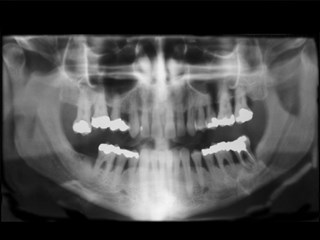

Översiktsröntgen som visar att benet runt tänderna har dragit sig tillbaka. Patienten har redan blivit av med en tand och fler kan det bli om inte behandling sätts in. Det vita på bilden är lagningar.